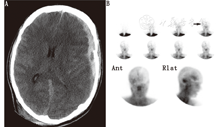

(3)非脂溶性放射性药物。主要的放射性核素显像脑血流研究使用非脂溶性放射性药物,如99Tcm-二乙撑三胺五乙酸(diethylene triamine pentaacetic acid, DTPA;图1),99Tcm-葡庚糖酸盐和99TcmO4- (图2),其不能通过血-脑屏障[67,68]。采用肾脏放射性药物是因为显像剂本身血液清除相对较快,可以满足重复检查的需要,并且对影响诊断的重要组织结构不会造成明显放射性覆盖。注射药物后立即观察血流相,可见大脑前动脉和大脑中动脉存在血流显影(图1),而在同样足够的药物注射后,无脑血流显影(图2)。由于头皮静脉侧支循环,即使在脑死亡的情况下静脉窦也可以显像[69,70,71]。

(4)脂溶性放射性药物。从20世纪80年代中期开始[72,73,74],脂溶性放射性核素99Tcm-HMPAO[75,76,77,78,79]和99Tcm-bicisate[47,48,80]跨越血-脑屏障经相关代谢后滞留于脑间质,从而可用于诊断脑死亡。即使在代谢功能紊乱时,此类探针也可滞留于脑间质[78,79]。其与4支脑血管对比造影术有较好的相关性[81]。通过显像可获得早期血流相和随后的血池相;但只要其中任何一相有血流存在,则均不支持脑死亡诊断(图3,图4)。99Tcm-HMPAO分解较快,需在30 min内注射[82]。随后开发的稳定制剂具有更长的贮存期,但注射时需先通过直径为0.45 μm的过滤装置以排除颗粒物质[83];必须注意确保过滤不妨碍足够的"弹丸"注射剂量。

静态血池相更为灵敏,且重要的是其对后颅窝的评估能力(图5);动态血流相主要反映脑前部情况,不能反映血池相信息[79,84]。临床研究主要使用延迟显像来评估脑血流灌注情况[77,78,85,86]。de la Riva等[79]的研究表明血流相无法显示的血流情况在静态血池相中小脑灌注很清晰。此外,由于血池相较血流相可以获得更高的放射性计数,因此图像的灵敏度更高。血池相对"弹丸"注射技术和注射时间的依赖性较小;还可进行重复显像及断层显像[87,88,89]。除外血池相无显像的罕见情况,99Tcm-HMPAO准备失败会导致动态血流图像的摄取值持续残留[20,78,79,80,81,82,83,84,85,86,87,88,89,90]。